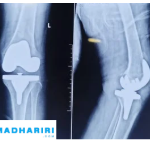

محمي: Knee Surgery جراحة الركبة